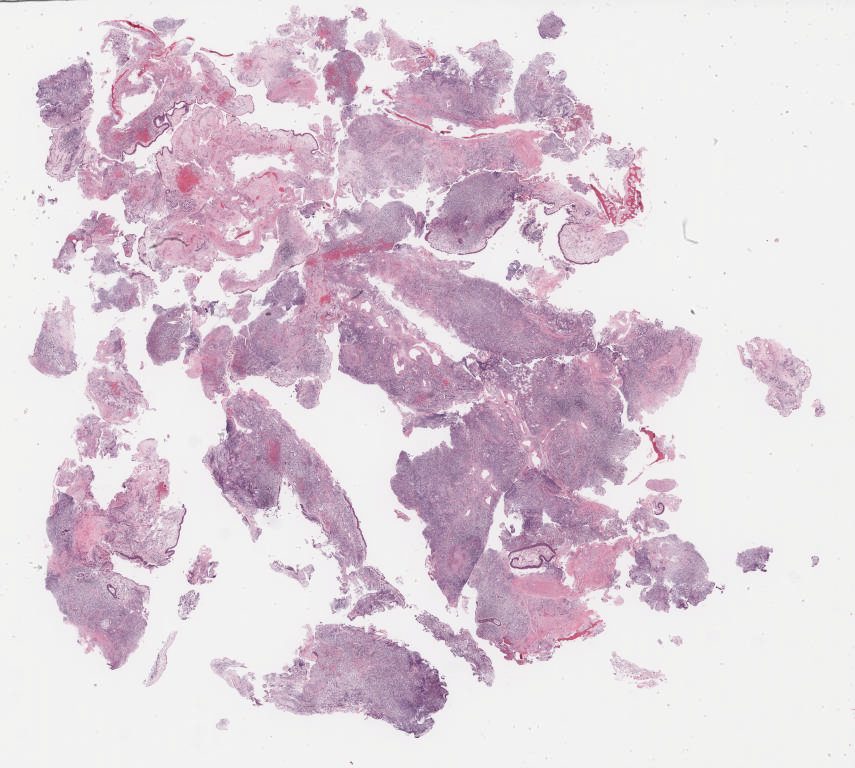

Case2.svs

65736

x

70499

@

40X